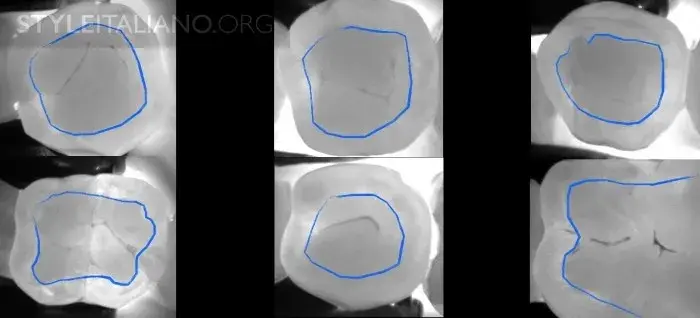

Рис. 3 Устройство Diagnocam, в основе которого лазерно-индуцированное просвечивание, позволяет нам просветить жевательные поверхности зубов. Выражается в серой шкале. Различные ткани зуба реагируют на свет по-разному: эмаль светлая, дентин более серый, а полости гораздо темнее.

Рис. 4 – Эта технология позволяет найти кариес на ранней стадии. Ткани серого цвета нуждаются в мониторинге.

Рис. 7 – Необходимо объяснить пациенту, где эмалево-дентинная граница и в каком случае поражение необратимо.

Рис. 8 – Фиссура - одна из анатомически сложнейших областей зуба. Мы можем получить представление о происходящих в ней процессах - фиссурном кариесе.